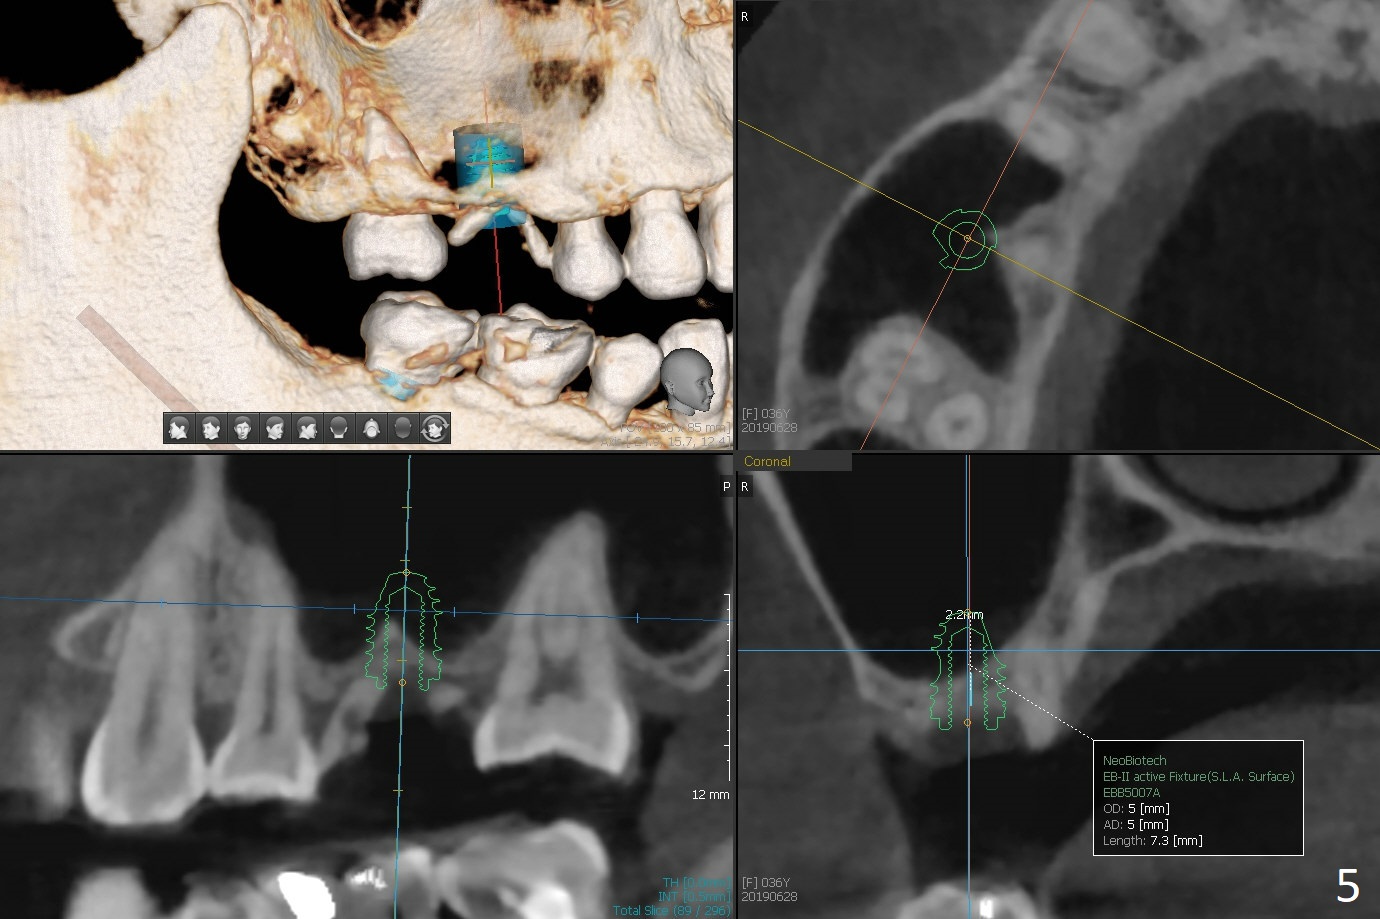

A 36-year-old woman is nervous about dentistry. She will take Valium by herselft before surgery (Fig.1). The tooth #3 has 3 residual roots (Fig.2 (CBCT 3 D occlusal view)). The bone is 2-3 mm thick (Fig.3,4 (sagittal, coronal sections)). A 5x7.3 mm implant will be placed with IS guide (Fig.5 (12 mm offset)). Since IBS implants are able to achieve amazing stability in the thin bone, prepare the shortest 4-5 mm in diameter dummy implants (IS (better surface treatment) and IBS) after sinus lift using UF Guided Sinus Lift Approach Kit (surgery). With intact tooth structure at #14, the bone height is not much (Fig.6), congenital (genetic) in nature. The infection at #31 is more severe (Fig.7). Extraction will be the 2nd in order. Because of limited bone, it is better to do bone graft first. The patient is concerned about the discolored upper right canine, which should be associated with orthodontics 20 years ago (take photos). The apical canal is obliterated (Fig.8,9 arrow) with periapical radiolucency (arrowhead). In fact the bone at #31 is so little that the tooth will be extracted for socket preservation.